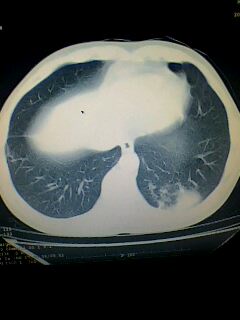

标题: CT28315:咳嗽咳痰咯血半月并胸痛 [打印本页]

标题: CT28315:咳嗽咳痰咯血半月并胸痛

1、纵膈窗效果不好,初步考虑左肺下叶感染性病灶,建议正规抗炎治疗后复查   2、右肺下叶陈旧性病灶伴局部胸膜增厚。

左下肺肿块影,深分叶,考虑肺癌。

左下肺球形病灶,考虑:1:球形肺炎;2:周围型肺癌不除外,建议治疗后复查

不排除左肺下叶周围型肺癌可能!建议穿刺活检!

考虑左肺下叶周围型肺癌并阻塞性肺炎。